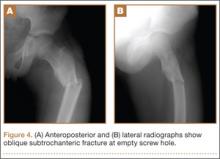

About 9 months after initial surgery, we removed 2 titanium screws, which were completely covered with growing new bone. The lateral cortex surrounding the screw heads was chiseled from the lower level of the lesser trochanter to remove the completely immersed screw heads (Figures 3A, 3B).